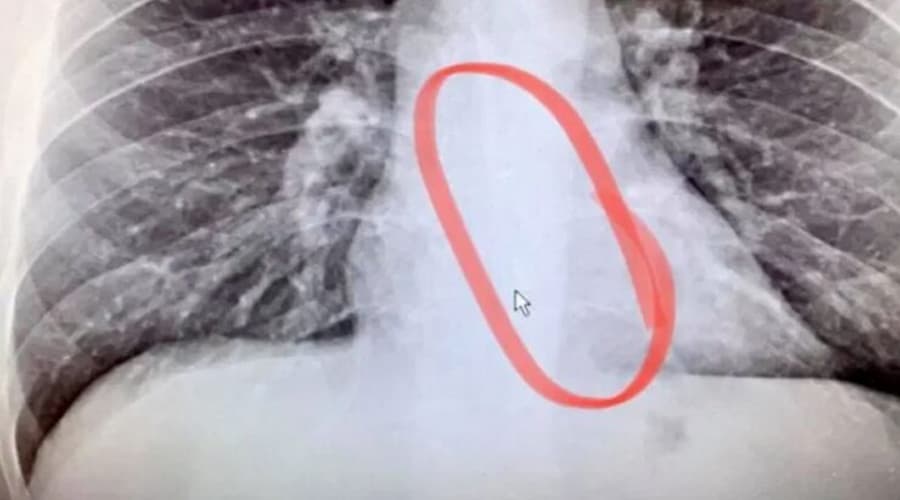

เมื่อได้รับผลการ X-Ray เข้าจึงพบว่าสิ่งที่ติดอยู่บริเวณหลอดลมของเขา คือ หูฟัง AirPods ข้างนึงที่หายไป โดยทีมแพทย์ช่วยเอามันออกมาได้อย่างปลอดภัย เคสนี้ถือว่าโชคดีมากๆ ที่กลืนหูฟังเข้าไปแล้วยังหายใจได้ปกติอยู่